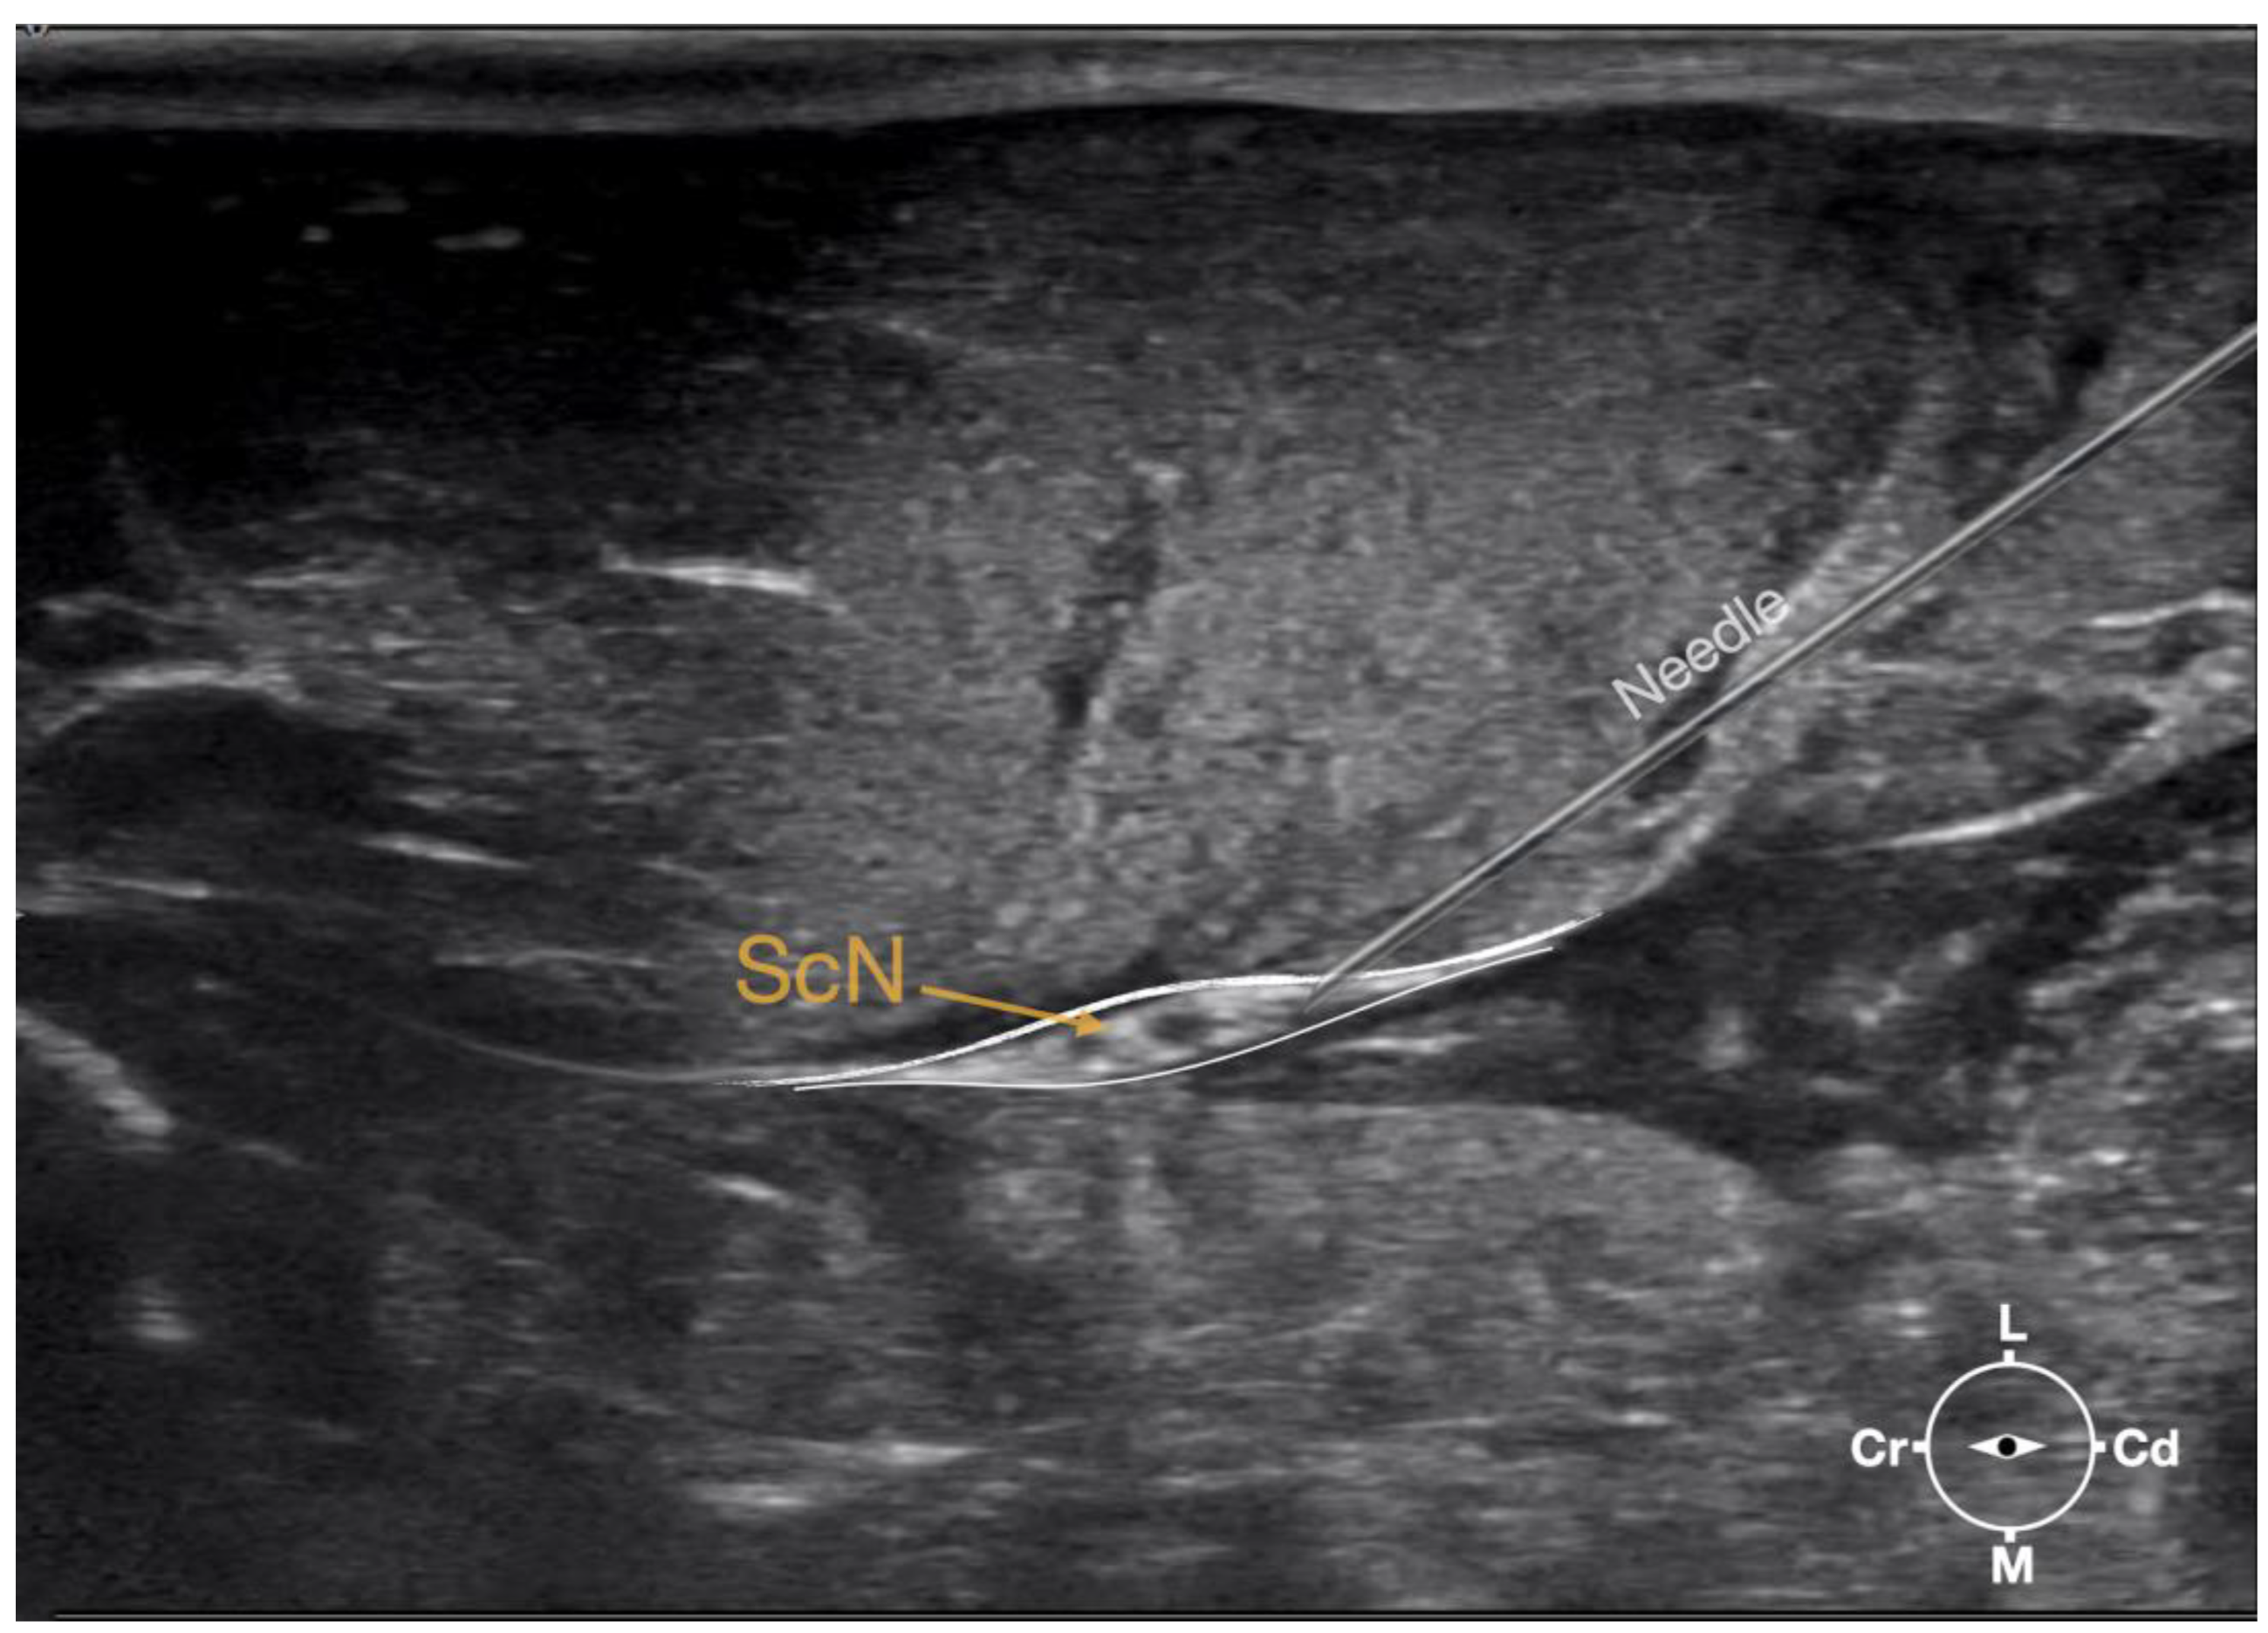

Figure 1. Corresponding transverse ultrasound image to the figure 2. The ultrasound image shows the sciatic nerve and related structures. The white lines indicate the muscular fascias enveloping the sciatic nerve. Cr, cranial, Cd, caudal; L, lateral; M, medial.

Figure 3. Ultrasonographic image showing the approach of the needle towards the sciatic nerve. ScN, sciatic nerve; Cr, cranial; Cd, caudal; L, lateral; M, medial.

Ultrasonographically, the sciatic nerve appeared as a binocular structure with a hyperechoic rim surrounded by the muscular fascias of the biceps femoris and adductor muscles at this level. All muscles were displayed as structures with heterogeneous echogenicity. The biceps femoris muscle was lying lateral to the ScN while the adductor muscle was medial to the ScN. The femur was displayed as a hyperechoic structure with acoustic shadow and located cranial to the ScN nerve.